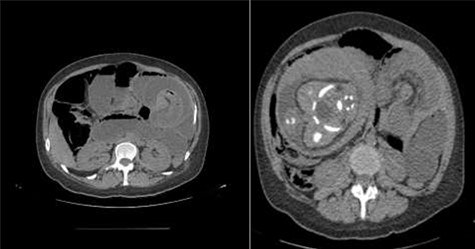

Physical examination presented normal vital signs. The abdomen was tender but lacked signs of peritonitis. Blood analysis revealed leukocytosis, neutrophilia and elevated lactate dehydrogenase. Obstetric ultrasonography (US) showed: fetus at cephalic presentation with good vitality, regular amniotic fluid volume, placenta without detachment. An abdominal computed tomography (CT) scan revealed proximal jejunal dilation caused by an ileoileal invagination and collapsed distal ileum (Figs 1 and 2). Betamethasone and atosiban were administered, and a supraumbilical laparotomy was performed. The intussusception in the common limb (80 cm distal to jejunojejunostomy) (Fig. 3) was reduced (Figs 4 and 5) with progressive and complete intestinal vascular perfusion (Fig. 6). The postoperative period was uneventful, and a caesarian was performed 4 weeks later. At the 45-month follow-up, there was no recurrence.

Retrograde intussusception of the common limb into the jejunojejunostomy.